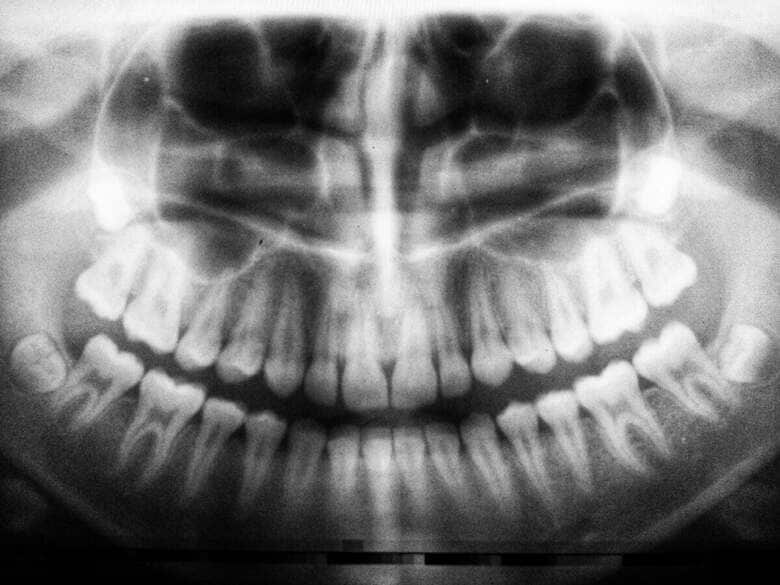

<歯科矯正のために歯医者を訪れた親子が目にしたのは、驚きのレントゲン写真だった>

「矯正歯科医が部屋に戻ってきて、X線画像をスクリーンに映したの。私たちは同時にそれを見て、しばらく何を見ているのか理解できなかった」と母親は本誌に語っている。

■副鼻腔に引っかかっている「まさかの物体」の正体は?...本文記事で詳しく読む

「矯正歯科医が部屋に戻ってきて、X線画像をスクリーンに映したの。私たちは同時にそれを見て、しばらく何を見ているのか理解できなかった」と母親は本誌に語っている。

■副鼻腔に引っかかっている「まさかの物体」の正体は?...本文記事で詳しく読む